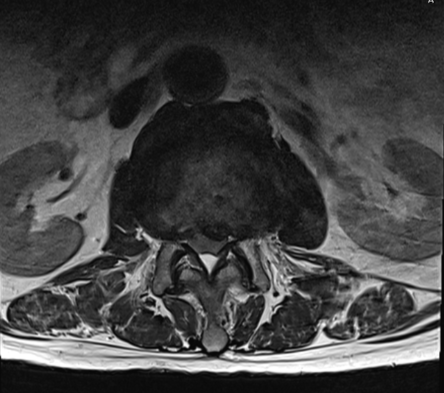

第1腰椎陳旧性圧迫骨折・腰椎の各椎間板狭小化/椎体変形/骨曲形成/ヘルニア/黄色靭帯肥厚/脊柱管狭窄症・股関節炎

左縮瞳低下・左股関節内旋制限・徒手筋力検査/左L5レベル低下